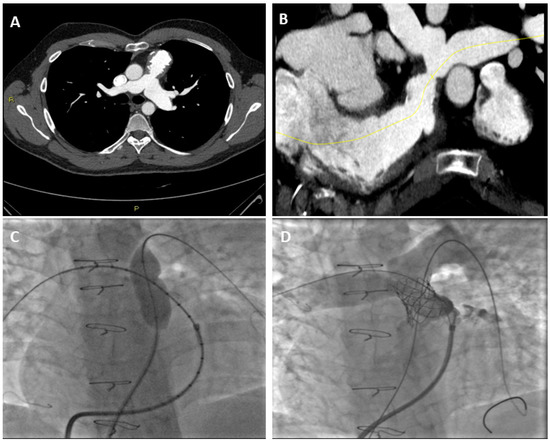

3. Role of CT on Pulmonary Stenosis and Regurgitationt Assessment

3.1. Pulmonary Stenosis and CT

3.2. Pulmonary Regurgitation and CT

3.3. Right Ventricle Assessment with Cardiac CT